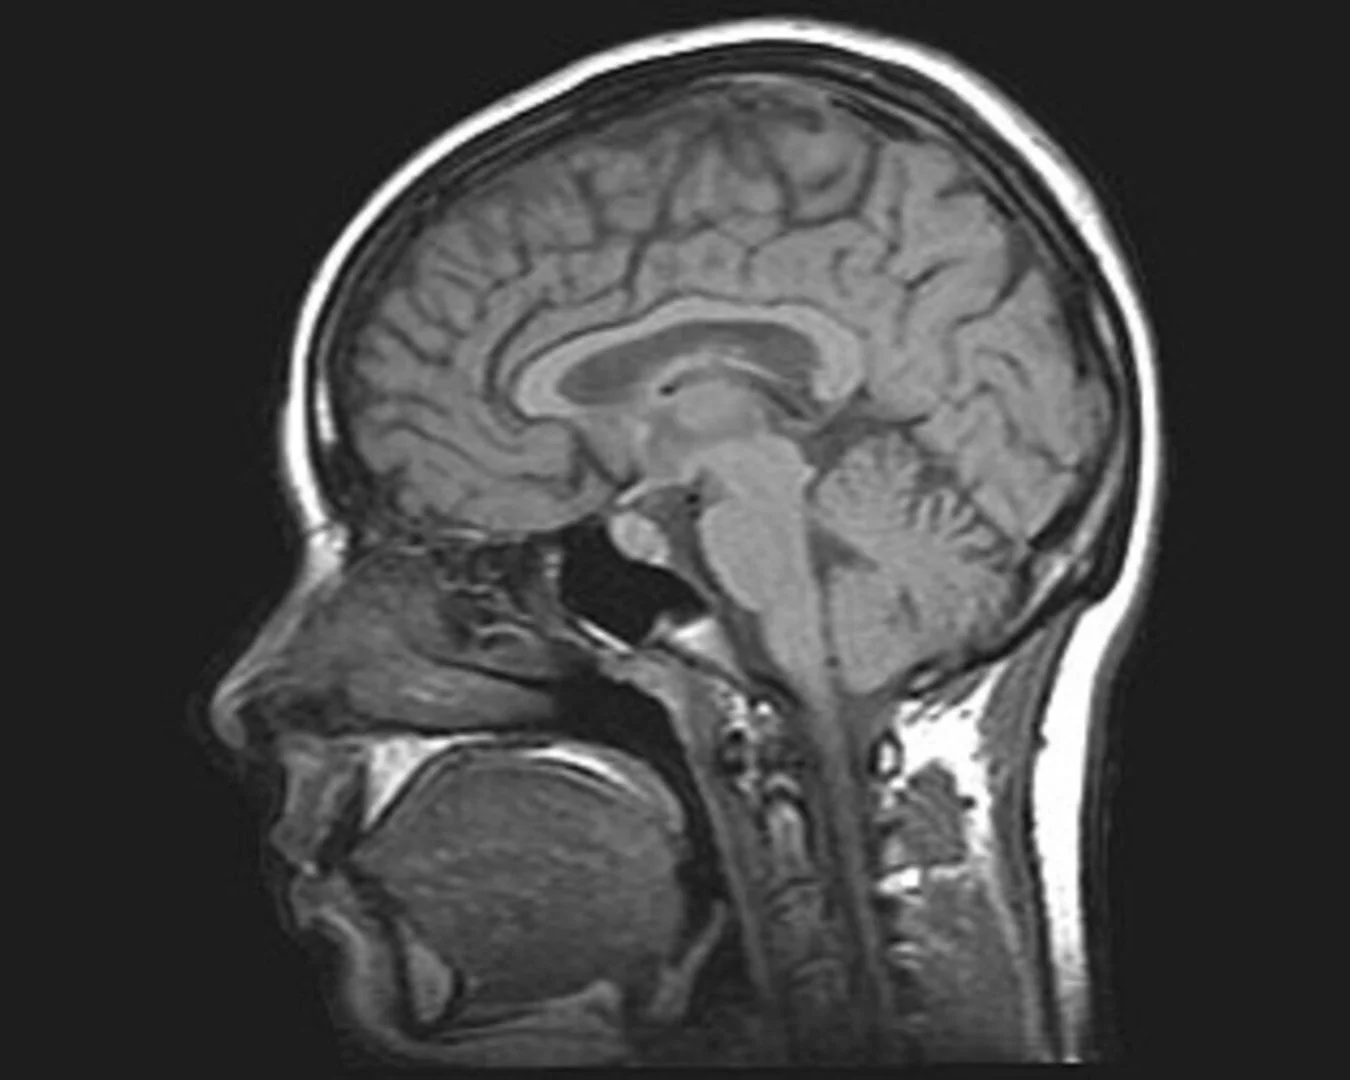

• People with cerebellar ataxia